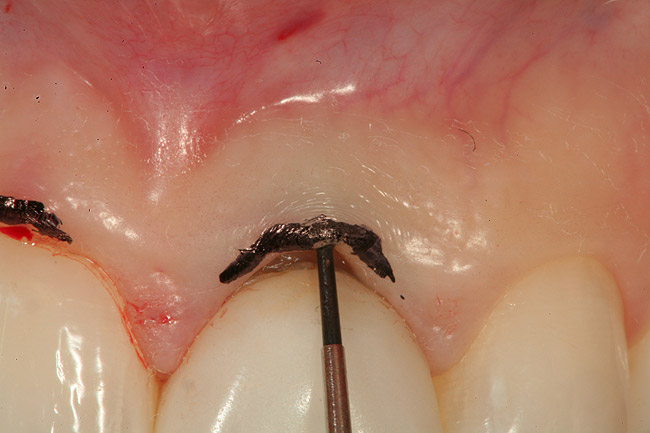

Figure 5  The needle electrode is shown removing the marked tissue to balance the gingival heights.

Figure 5

Again, use the needle electrode on the electrosurgery unit to limit the zone of necrosis. It is the author’s opinion that troughing is an excellent adjunct to mechanical retraction and most of the time when troughing, he will “lay” a cord in the sulcus after troughing to help push away any small tissue tags that can remain and further aid in hemostasis. The goal of retraction is to have a “moat around the castle,” or unimpeded access to the sulcular area for the impression material to flow. The maxillary premolar in Figure 11 had a post and core placed and is ready for master impression. Due to the subgingival margin position on the lingual aspect of the preparation and thickness of the interproximal tissue, the proximal and lingual aspects of the preparation were troughed with the electrosurgery needle electrode (Figure 12 and Figure 13). After sounding to the crest of bone to verify that biologic width was not encroached upon (Figure 14), a #1 retraction cord soaked in a hemostatic agent was “laid” into the sulcus (Figure 15). The only “packing” of cord took place on the facial where due to the thinness of the tissue, troughing was not done. Figure 16 shows a totally patent gingival sulcus with no signs of hemorrhage, ready for placement of impression material. Figure 17 shows a master impression taken after a troughing/retraction procedure on tooth No. 5.